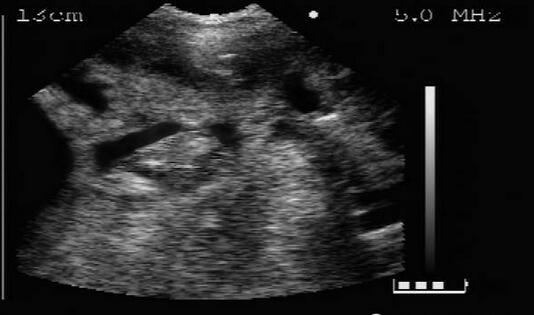

膀胱及卵巢检测图(1/7)